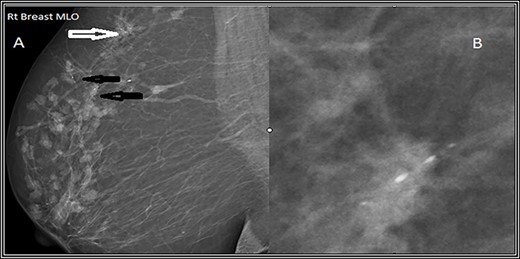

Mediolateral oblique (MLO) mammographic view of the right breast. (A) Shows multiple foci of microcalcifications arranged in linear distribution (black arrows) and others in clusters (white arrows). (B) Spot magnification view of the most suspicious lesion shows linear fine microcalcifications.

US follow-up after the first biopsy revealed several findings: (A) the most outer lesion can be seen at 9:00 and became vertically oriented inside the breast parenchyma with irregular serrated margins; it infiltrated the adjacent breast parenchyma and the deep posterior acoustic shadow. (B) A tiny microcalcification can be seen at its upper pole. (C and D) An enlargement of the previously seen mass lesions after a second biopsy in which all of them have microlobulated borders and are longitudinally oriented inside the breast tissue can be observed.